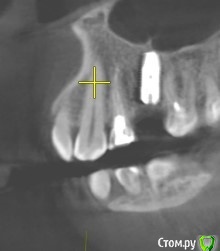

Tatiana72 Опубликовано 27 октября, 2020 Автор Поделиться Опубликовано 27 октября, 2020 Добрый вечер!Выкладываю скрины срезов Ссылка на исследованиеhttps://yadi.sk/d/ViQR0U6R2QjHzg Ссылка на комментарий

Дмитрий М Опубликовано 28 октября, 2020 Поделиться Опубликовано 28 октября, 2020 Добрый вечер!Выкладываю скрины срезовImage4.jpgImage5.jpgImage9.jpg Ссылка на исследованиеhttps://yadi.sk/d/ViQR0U6R2QjHzg не волнуйтесь всё хорошо, по КТ корень зуба не задетесть небольшой очаг разряжения на одном из апексов, обратитесь к стоматологу 1 Ссылка на комментарий